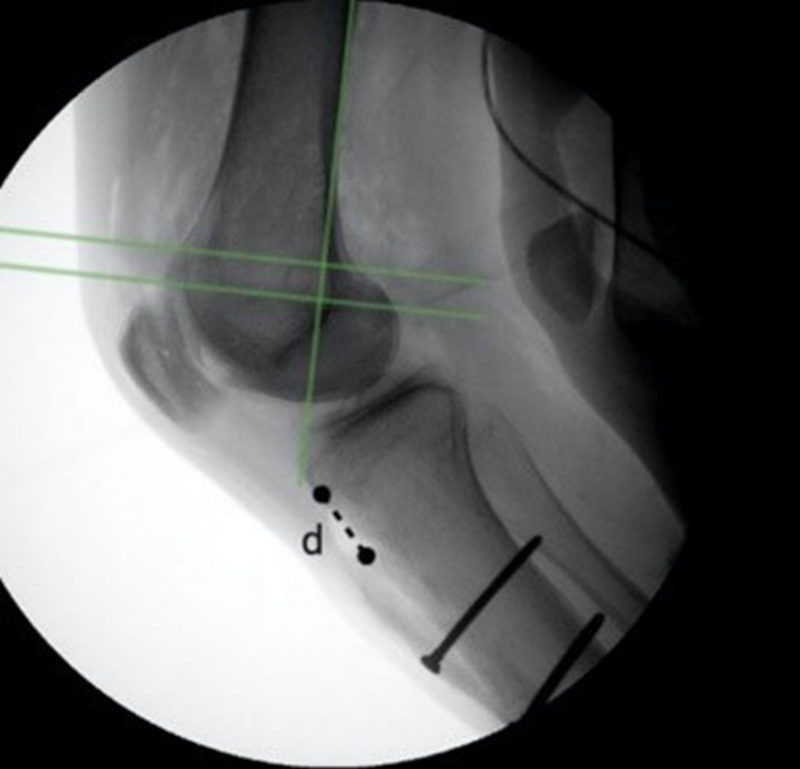

对于复发性髌骨脱位合并股骨前倾角增加的情况,张志军等人分析126例此类患者,发现MPFLR联合股骨远端去旋转截骨术(DDFO)组的患者相较于单纯MPFLR组的患者有更高的Kujala和Lysholm评分,更低的残余移植物松弛率[14]

图8